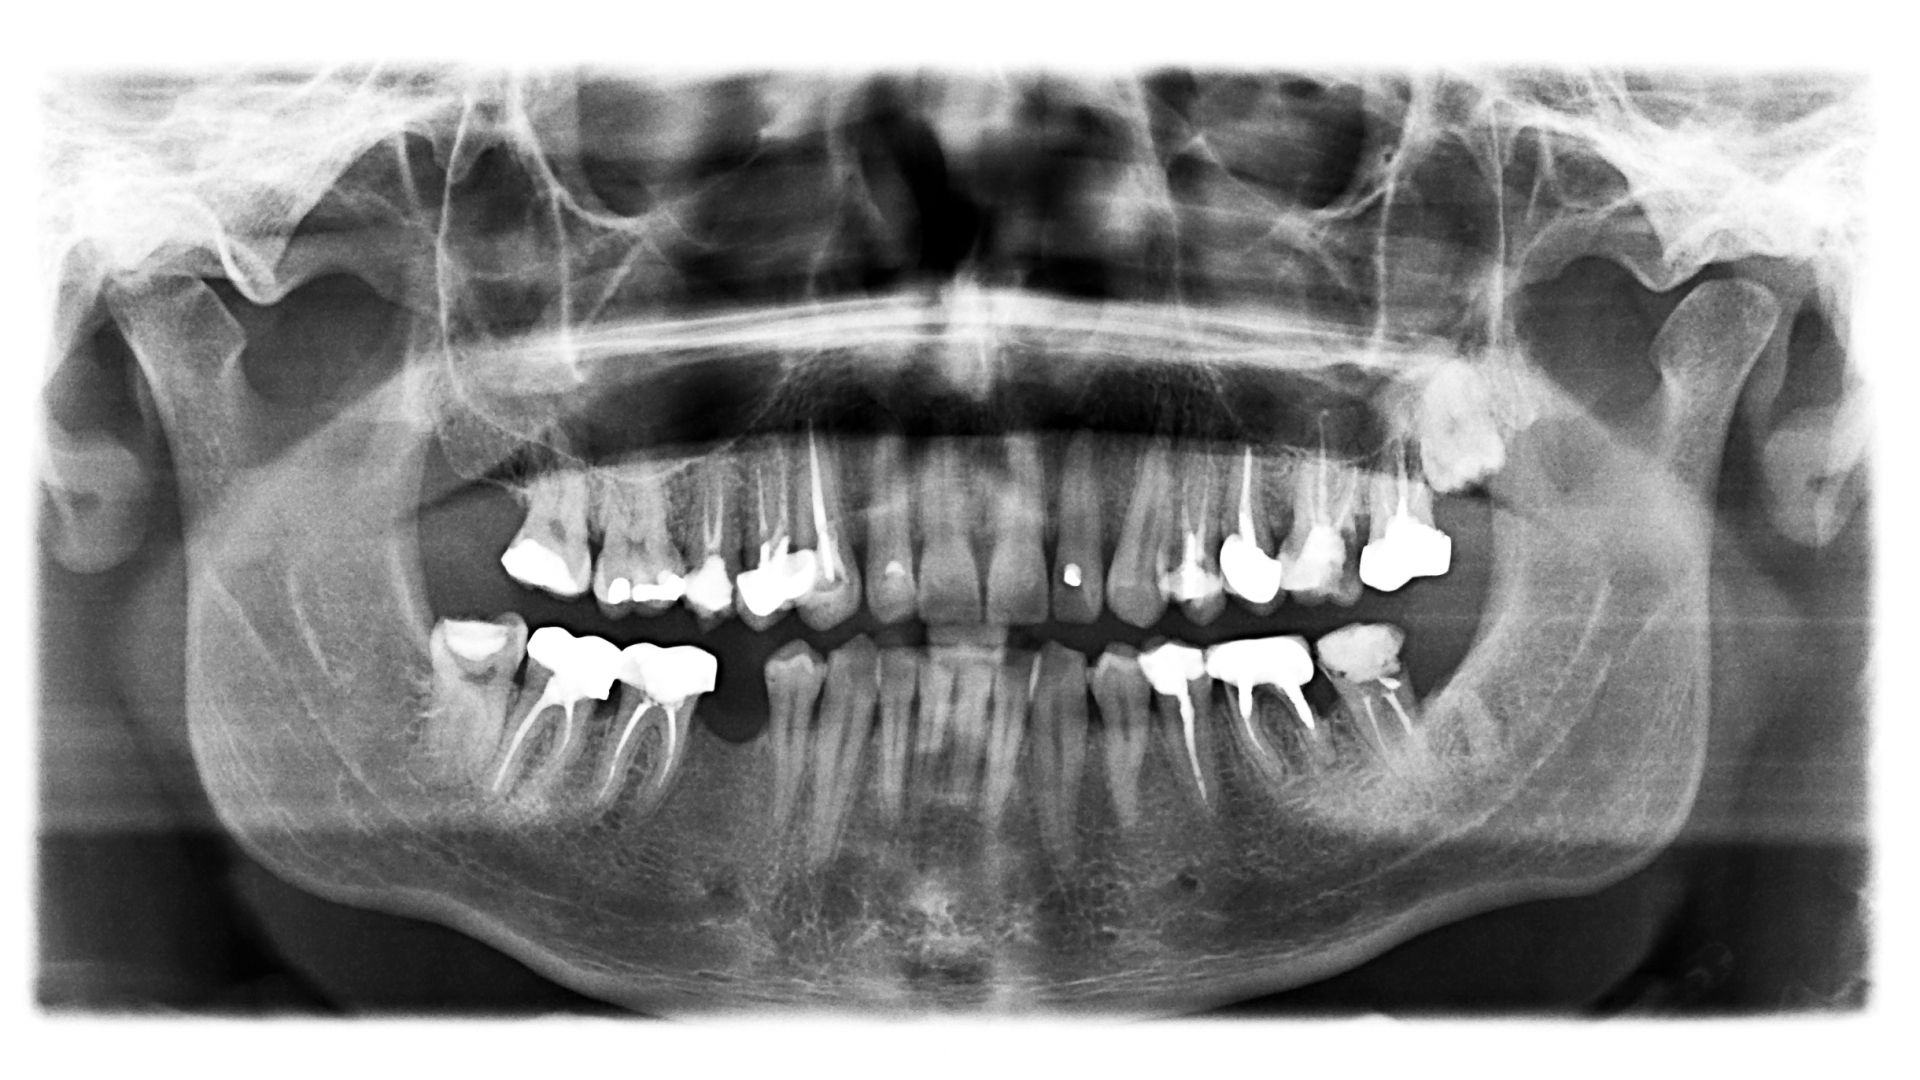

10. Panoramic Imaging Pocket Dentistry Conventional Dental Imaging Conventional dental radiography remains an important everyday tool in spite of the rise of sophisticated cbct imaging technology. The current dental examinations consist of intraoral imaging with digital indirect and direct receptors, while extraoral imaging is. Intraoral and extraoral, analogue and digital, ionizing and non. Dental imaging modalities give insights into teeth growth, bone structures, soft. Broadly, imaging techniques used. Conventional Dental Imaging.